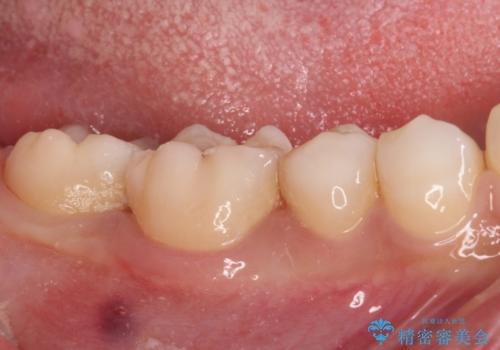

レントゲン写真などから、速やかに処置を行うべき歯が2歯あったため、それぞれセラミックインレーとPGAインレー(ゴールドインレー)にて修復治療を行うこととしました。

どちらの歯も痛みなどの症状はなく、治療後も異常所見なく経過をたどっています。

上顎大臼歯は向かい合った人から見えることはほとんどないため、切削量が少なく、適合の良いゴールドインレーが大変おすすめとなります。